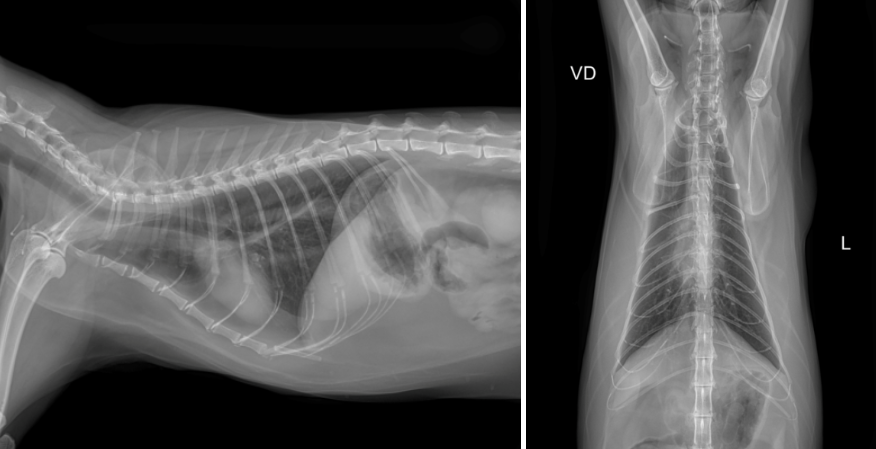

x-ray 검사상 특이소견은 확인되지 않았습니다.